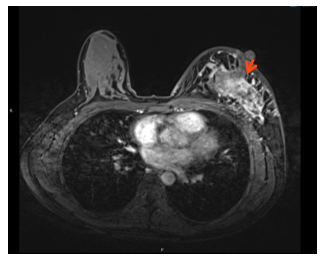

3.头增强MRI:左枕叶强化结节(长径1.3cm,靶病灶2),周围伴水肿,转移可能。(图3)

图3 头增强MRI

2.靶病灶2(脑转移病灶)评效:2周期部分缓解PR,4周期病灶持续缩小,评效PR,6-8周期病灶消失,疗效达CR。(图8)

图8 靶病灶2(脑转移病灶)评效CR